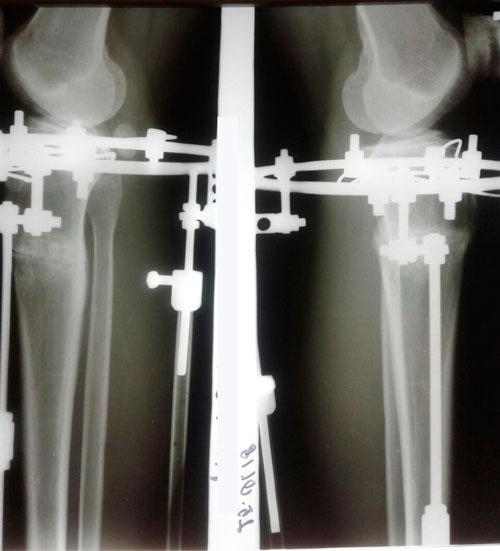

на фиксации.

рентген перед фиксацией.

IMG-20171026-WA0014.jpg